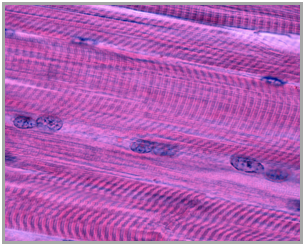

Muscle tissue is a specialized type of tissue in the body that plays a crucial role in movement by contracting and generating force. The primary function of muscle is to convert chemical energy, primarily stored in the form of adenosine triphosphate (ATP), into mechanical energy, which results in movement. Additionally, muscle activity generates heat, contributing to the maintenance of body temperature, a concept previously discussed in the context of homeostasis.

All muscle tissues share four fundamental properties that enable their function. The first property is contractility, which refers to the ability of muscles to forcibly shorten. For example, when the biceps contract, the arm bends, demonstrating how muscles create movement through shortening. The second property is extensibility, meaning muscles can stretch when pulled. This property allows muscles to elongate without damage, as seen in activities like yoga.

The third property is elasticity, which indicates that muscles can return to their original length after being stretched or contracted. This is similar to how a rubber band behaves, returning to its initial size after being stretched. Finally, the fourth property is excitability, which allows muscle cells to respond to stimuli. Muscle cells can transmit signals through action potentials, similar to the nervous system, enabling them to know when to contract.

Understanding these properties—contractility, extensibility, elasticity, and excitability—provides a foundation for exploring how muscle cells receive signals to contract, how they propagate these signals, and the mechanisms behind muscle contraction itself. This knowledge is essential for comprehending the muscular system's role in movement and overall body function.